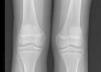

Las radiografías de cráneo se observaron normales, aunque los estudios de huesos largos con evidencia de descalcificación (fig. 2).